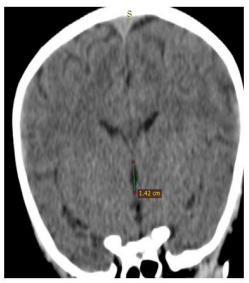

| Figure 1: Axial CT image of the brain showing the maximum width of the third ventricle |

Third ventricle was marked as a mid-line structure between right and left thalami. Width of third ventricle was measured in mm (millimeters) at the level of interventricular foramen (foramen of Monro) and was taken as the maximum distance between the two thalami at this level. The height of the third ventricle could not be measured as its posterior marker the pineal gland was not seen in CT scan sections of all patients. The maximum third ventricular width (Figure 1) and the maximum third ventricular height (Figure 2) were measured in mm. The data were entered into Ipinfo, version 7 and analyzed using the IBM SPSS Statistics, version 20. The means (± standard deviation), ranges, minimum, maximum, and the 95% confidence intervals for the mean (in order to include the true population, mean in 95% of the cases) were all calculated. P- Value less than 0.05 is considered as statistically significant.